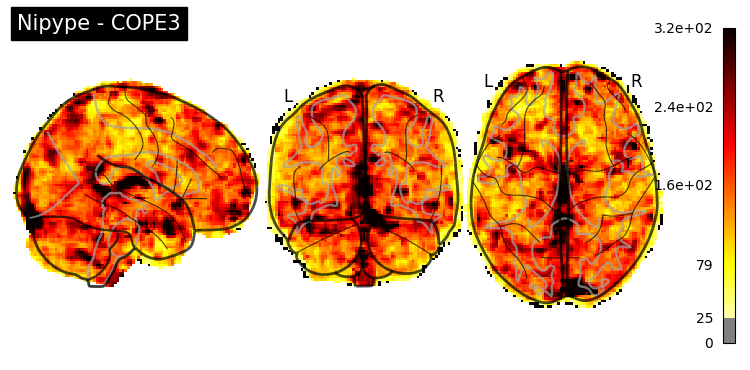

The first-level GLM#

Here we randomly choose the four copes from subject-09 run-1

nipype_cope1 = './output_level1/level1_results/09/results_dir/_subject_id_09/_level1estimate0/results/cope1.nii.gz'

nipype_cope2 = './output_level1/level1_results/09/results_dir/_subject_id_09/_level1estimate0/results/cope2.nii.gz'

nipype_cope3 = './output_level1/level1_results/09/results_dir/_subject_id_09/_level1estimate0/results/cope3.nii.gz'

nipype_cope4 = './output_level1/level1_results/09/results_dir/_subject_id_09/_level1estimate0/results/cope4.nii.gz'

plotting.plot_stat_map(nipype_cope1, bg_img=nipype_cope1, title = 'Nipype - COPE1', cmap = 'bwr', colorbar = False)

plt.show()

plotting.plot_stat_map(nipype_cope2, bg_img=nipype_cope1, title = 'Nipype - COPE2', cmap = 'bwr', colorbar = False)

plotting.plot_stat_map(nipype_cope3, bg_img=nipype_cope1, title = 'Nipype - COPE3', cmap = 'bwr', colorbar = False)

plotting.plot_stat_map(nipype_cope4, bg_img=nipype_cope1, title = 'Nipype - COPE4', cmap = 'bwr', colorbar = False)

../../_images/a7f7f387884673a96e62aa7d2d938a6b6487846759bc4500b6d0cff677c7358d.png ../../_images/bc743ce13891ebab23c9f6c7d4d668db8d11c9409d4f6e4580f7d63b35ecdb77.png ../../_images/228b3b22c00177a8ad5dc1793cbbc90dbfb495735196a4af47e73b899de0ca82.png ../../_images/babe8f68f0856f0f1608dfe550483d8ca862aae33a659d1f970a9fbe726f3bb1.png